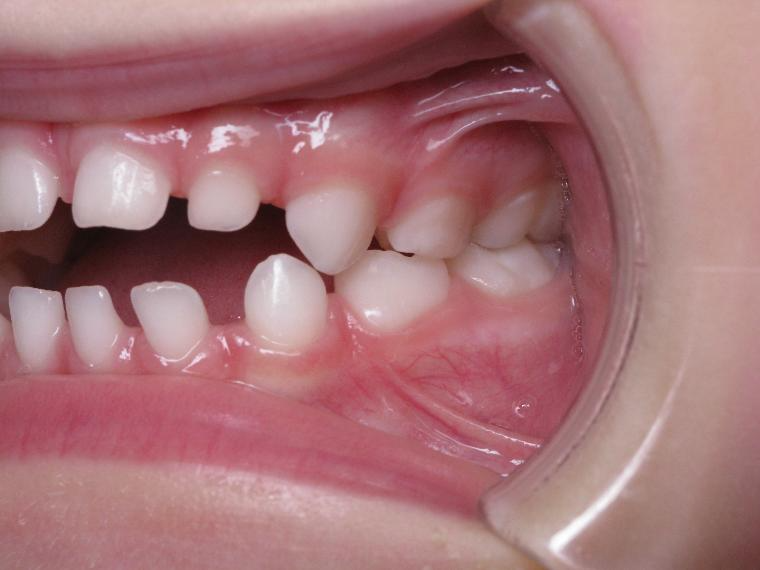

inversion postérieur coté droit et espace entre les dents du haut et du bas (diastèmes)

appareillage mobile pendant 35 mois

surveillance évolution de la dentition pendant 5 ans